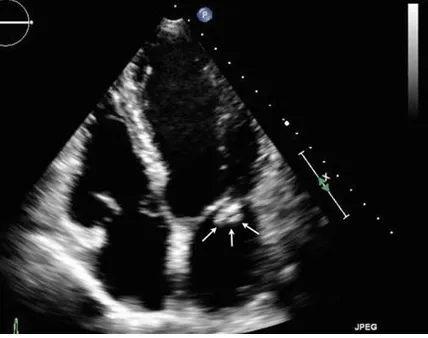

58세 남성이 10일 전부터 시작된 불규칙한 발열을 호소하며 내원했다. 청진 시 미상의 심장잡음이 관찰된다. 심장 초음파 검사와 손가락 및 손톱의 사진이 첨부되어 있다. 이 환자에서 의심되는 진단은 무엇인가?

발열과 심잡음 소견이 있다면 감염성심내막염을 반드시 의심한다. 손가락의 Janeway lesion(출혈성 반점), 손톱의 splinter hemorrhage가 관찰되며 심장초음파에서 vegetation이 관찰되기 때문에 감염성 심내막염으로 진단할 수 있다.

• 심장의 점액성 종양 : primary cardiac tumor 중 가장 흔한 cardiac myxoma는 LA에서 75%, RA에서 20% 관찰되며 심방에 위치하여 MS 또는 MR의 증상을 보인다. 위 지문의 사진도 LA에 위치하고 있으나 감염성 심내막염의 특징적인 임상 소견들이 있기 때문에 R/O할 수 있다.